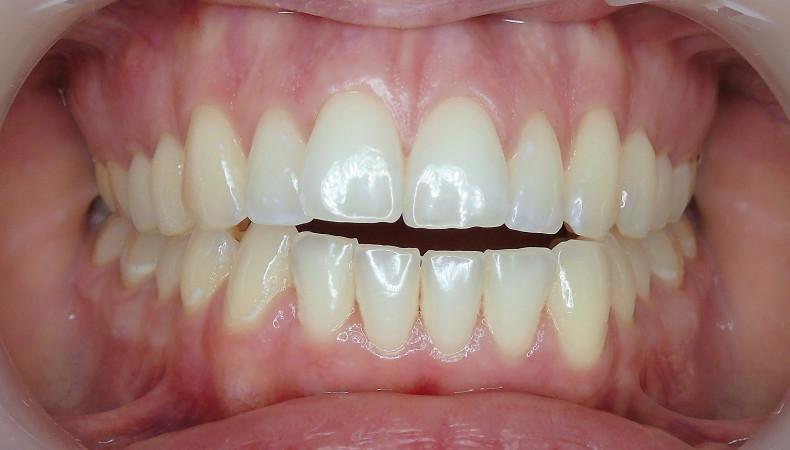

Sechs Monate nach Abschluss der Therapie besteht weiterhin ein stabiles Ergebnis. Wie im Vergleichsbild (Abb. 5a–c) zu sehen ist, konnte die geplante vertikale Korrektur vollständig erzielt und die Mittellinie bis auf eine MLV von 1 mm nach rechts im UK korrigiert werden.

Somit kann gezeigt werden, dass auch ohne operativen Eingriff oder festsitzende Apparaturen in kürzester Zeit ein ästhetisch und funktionell zufriedenstellendes Ergebnis erzielt werden kann (Abb. 6a–c; Abb. 7a–e). Es wird daher nachvollziehbar dargestellt, dass bei entsprechender Indikation Aligner für die Behandlung frontal offener Bisse eine hervorragende Alternative zu den konventionellen Behandlungsmethoden sein können. Voraussetzung für diesen Therapieansatz ist ein motivierter Patient mit guter Compliance.